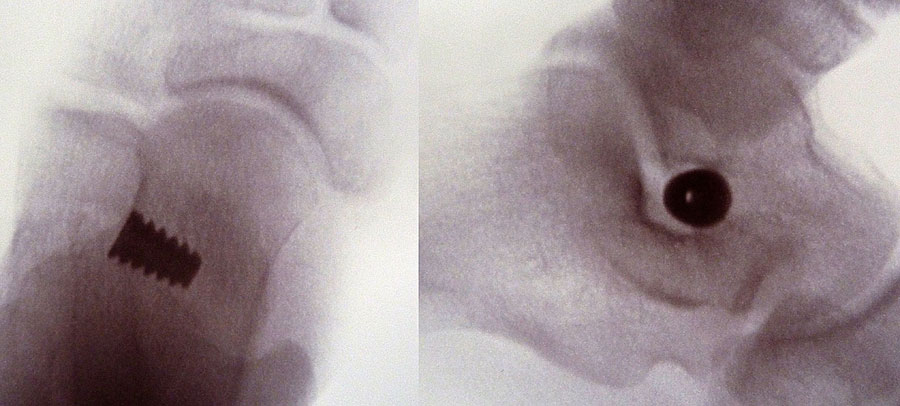

Röntgenkontrolle d.p. und seitlich unter Belastung nach 2, 6 und 12 Wochen und Beurteilung des Ergebnisses im Vergleich mit den präoperativen Bildern.

• Röntgenkontrolle d.p. und seitlich unter Belastung nach 2, 6 und 12 Wochen und Beurteilung des Ergebnisses im Vergleich mit den präoperativen Bildern (Abb.15).